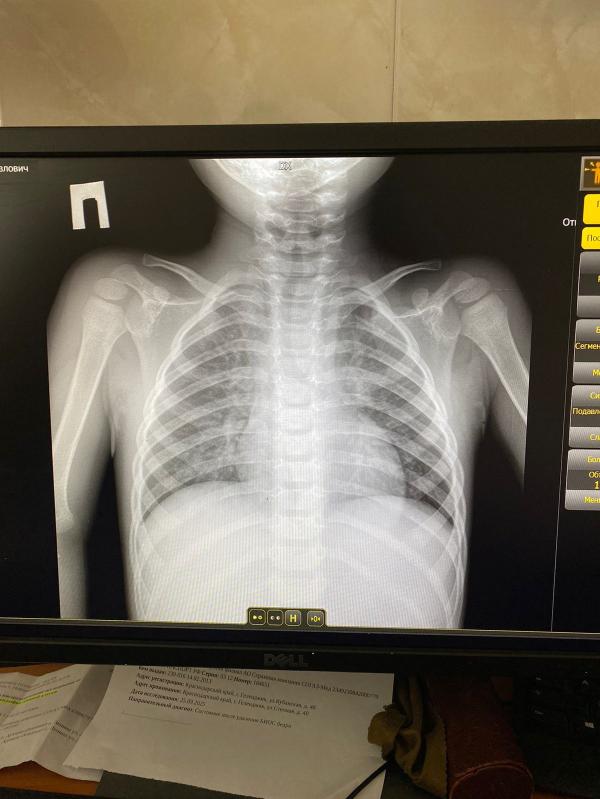

Что делать, если что-то в легких: советы мам

Девочки, есть ли что-то в легких и что вообще скажите ?🙏🏻🙏🏻🙏🏻

Я не спец по рентгену, но вроде бронхит. А что рентгенолог написал?